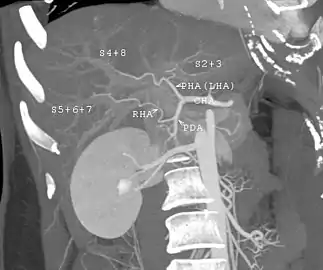

With the recent advances of noninvasive imaging, living liver donors usually have to undergo imaging examinations for liver anatomy to decide if the anatomy is feasible for donation. The evaluation is usually performed by multidetector row computed tomography (MDCT) and magnetic resonance imaging (MRI). MDCT is good in vascular anatomy and volumetry. MRI is used for biliary tree anatomy. Donors with very unusual vascular anatomy, which makes them unsuitable for donation, could be screened out to avoid unnecessary operations.

MDCT image. Arterial anatomy contraindicated for liver donation

MDCT image. Arterial anatomy contraindicated for liver donation MDCT image. Portal venous anatomy contraindicated for liver donation

MDCT image. Portal venous anatomy contraindicated for liver donation MDCT image. 3D image created by MDCT can clearly visualize the liver, measure the liver volume, and plan the dissection plane to facilitate the liver transplantation procedure.

MDCT image. 3D image created by MDCT can clearly visualize the liver, measure the liver volume, and plan the dissection plane to facilitate the liver transplantation procedure. Phase contrast CT image. Contrast is perfusing the right liver but not the left due to a left portal vein thrombus.

Phase contrast CT image. Contrast is perfusing the right liver but not the left due to a left portal vein thrombus.